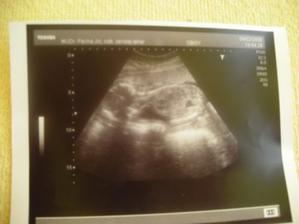

Tak máme za sebou utz, bobíček je v pořádku, pěkně nám vyrostl, máme cca 2100g,jsme hlavičkou dolů a odpovídáme 32+0...jen tak dál🙂)